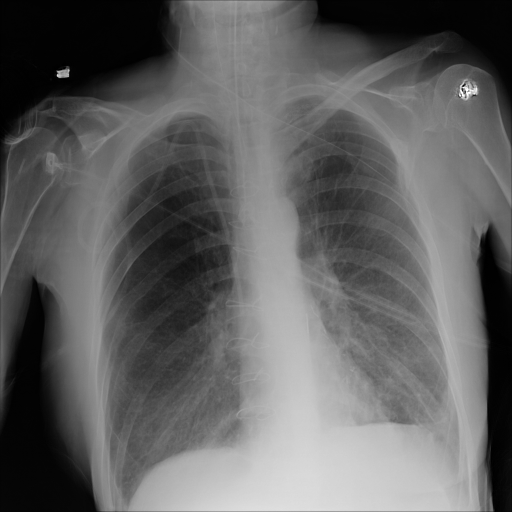

7.2 Qualitative assessment of LDP-processed CXR images

Here, we assume two possible privacy leakage scenarios. To CXR images, we intentionally add features that can lead to the re-identification of the subject appearing in a CXR image. The first feature is an artificial block marker. The second feature is a rare anatomical abnormality known as situs inversus simulated by flipping a CXR image along the vertical axis. Figs. 3(a) and 3(c) show CXR images with the artificial block marker. Fig. 5(a) shows a flipped CXR image to represent a case of situs inversus. We applied DP-GLOW to these CXR images. In Figs. 3(b) and 3(d), the image domain LDP fails to obfuscate the artificial block marker with a moderate privacy budget. In contrast, in Figs. 4(b) and 4(d), DP-GLOW successfully obfuscated the artificial block marker with the moderate privacy budget. On the other hand, the anatomical shape of the chest and the abnormal opacity (hilar regions in the case 1) are preserved. In Fig. 5(b), we observed that the right edge of the heart does not become obfuscated with the image domain LDP. In contrast, in Fig. 6(b), we observed that the right edge of the heart becomes obfuscated and the heart appears at the center of the thoracic cage with DP-GLOW. However, DP-GLOW with this privacy budget is insufficient to almost completely erase the feature of situs inversus.